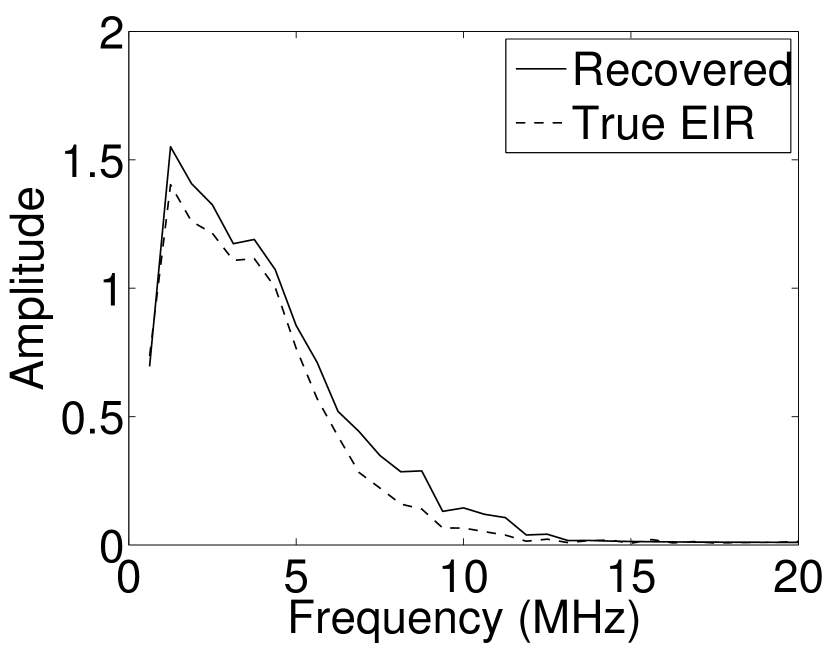

A 2D circular measurement geometry was employed. transducers were evenly distributed on a ring of radius mm that enclosed the phantom. The SOS was assumed to be constant and set at mm/s. Since the simulated data were formed by use of the C-D imaging model in Eqn. (2), no inverse crime was committed. The components of this vector corresponded to equally spaced temporal samples over the interval s. Subsequently, the noiseless voltage vector was obtained by convolving the pressure data with EIR-1 in Figure 1(b).

Each element in a real-world transducer array possesses its own EIR. In practice, the differences between the EIRs are sometimes neglected and an EIR corresponding to a single element may be used to represent all elements in the array. In some of the studies below, the EIR employed to initialize the VP algorithm (EIR-2 in Figure 1(b)) and the EIR employed to produce the simulated measurements (EIR-1 in Figure 1(b)) were experimentally measured from two different transducer elements in a circular transducer array (see Sec. VI-B). EIR-1 was measured by temporally integrating the PA signal produced by a point source positioned at the focus of the transducer. EIR-2 was measured by use of the method reported in [RNR2011]. In order to investigate the sensitivity of the VP algorithm to the initialization of the EIR, we employed different EIRs obtained by degrading EIR-1 as described later. When solving the sub-problem in Line-2 of Algorithm 1, was initialized as the zero vector. Algorithm 1 was terminated after 500 iterations, since it was observed that the changes in the reconstructed images with more iterations were negligible. When implemented by use of a single core of an Intel Xeon E5-2640 CPU, each iteration required approximately 7s to complete.

Figure 7(a) reveals that use of the inaccurate EIR in the conventional iterative method created strong artifacts and distortions. Figures 7(b) confirms that the artifacts and distortions were significantly mitigated when the VP method was employed. Image profiles for both cases are shown in Figures 7(c). The overall accuracy of the recovered EIR, shown in Figure 7(d) and 7(e), was improved, but it contained spurious oscillations.